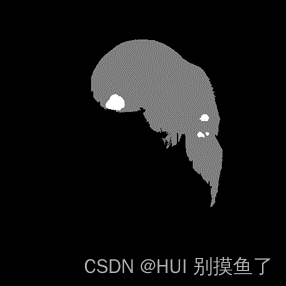

本文数据集为Lits2017肝脏和病灶的分割。标签为(0 1 2)。此数据集为增强CT,所以需要进行窗口的处理。具体参考【医学图像预处理过程】

注: 上面的标签图是自己赋值进行可视化的,实际是[0 1 2 ],根据自己数据集的情况查看mask值:

分析: 分割出肝脏(灰色)、肿瘤(白色),再加上黑色背景,相当于是一个三分类问题。

注:

-

灰度值:灰色128为膀胱内外壁,白色255为肿瘤。标签为 [0 128 255 ]。

-

任务:是要同时分割出膀胱内外壁和肿瘤部分,加上背景,最后构成一个三分类问题。